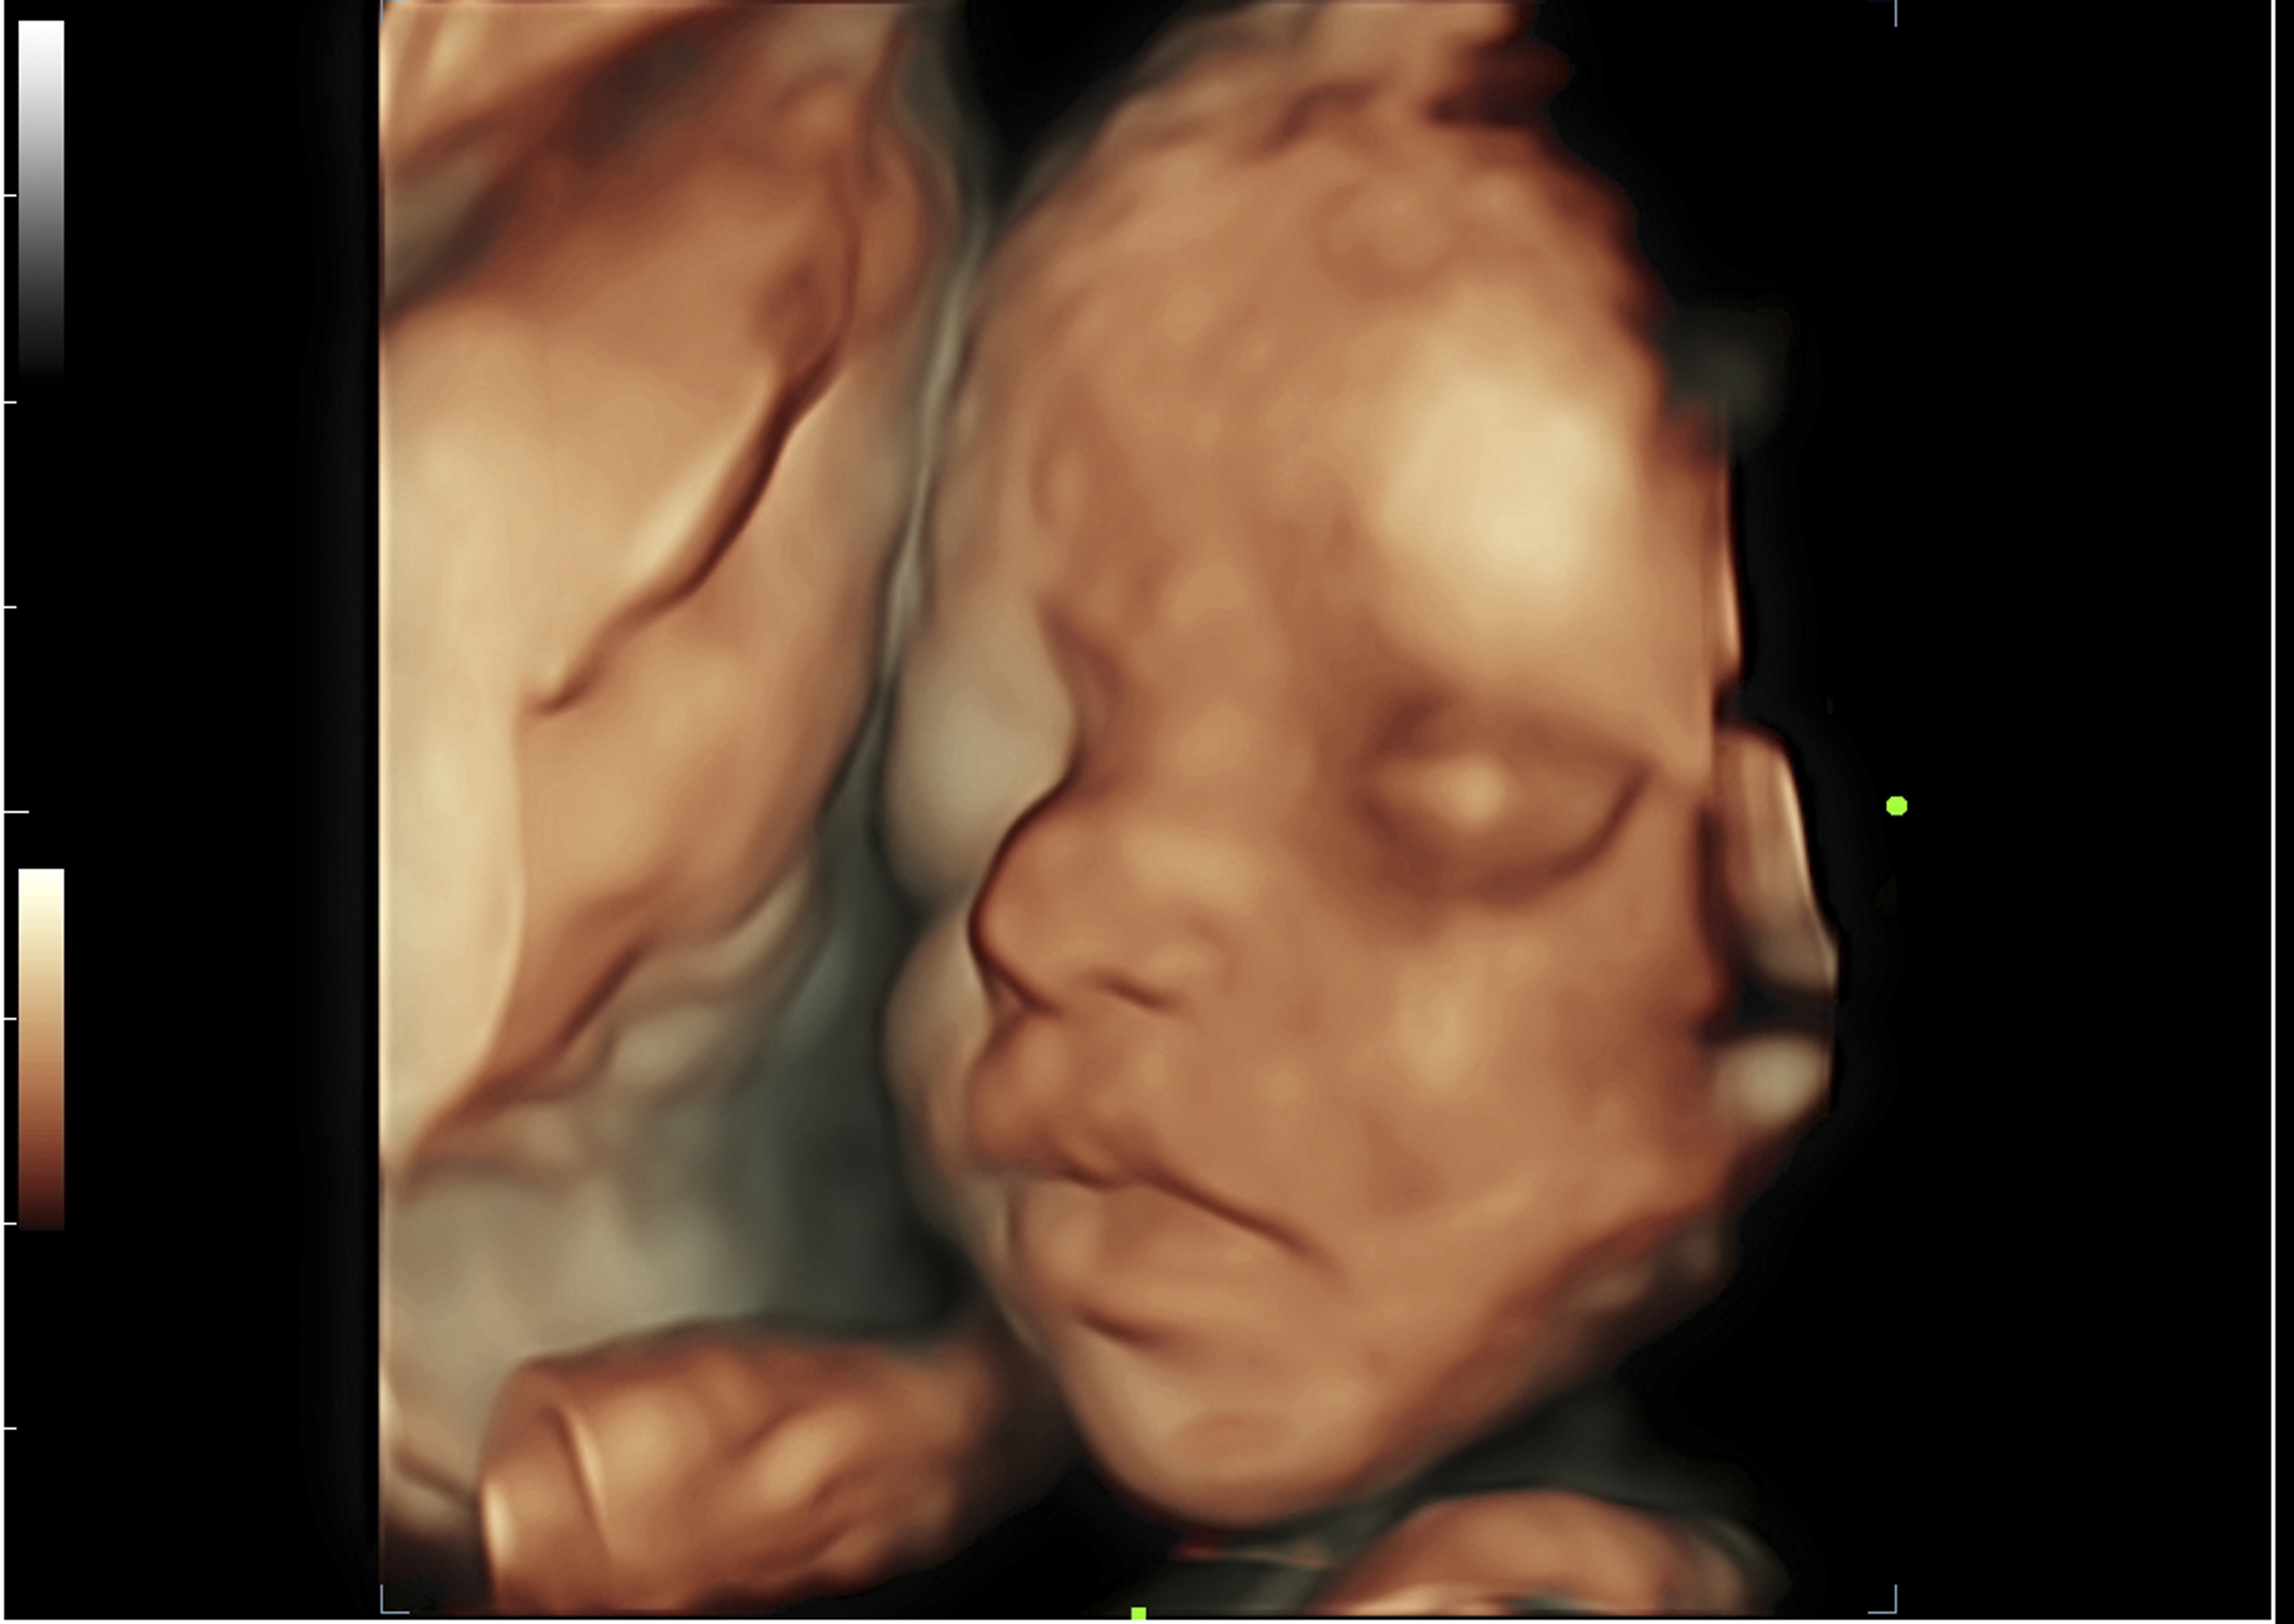

3D/4D Obestrics Scan

Ultrasound scans including 3D and 4D are more like a real-time photograph of your baby. With 3D scanning, many pictures of the child are taken in 2D and then merged to create a 3D image effect. With 4D scanning, pictures are made in real time and you can see what your child is doing in your womb at the time, such as moving of legs and arms or opening of the eyes.

Ultrasound scans are an essential tool to examine the health and internal organs of a growing fetus. It helps the gynaecologists to identify any complications. This identification allows doctors at Motherhood Hospitals to treat the baby at the earliest. These 3D/4D scans done throughout pregnancy, help the experts to detect any kind of anomalies such as a cleft lip, underdeveloped limbs helps you keep a track of spinal problems and other congenital disabilities. It also helps in monitoring the amniotic fluid.